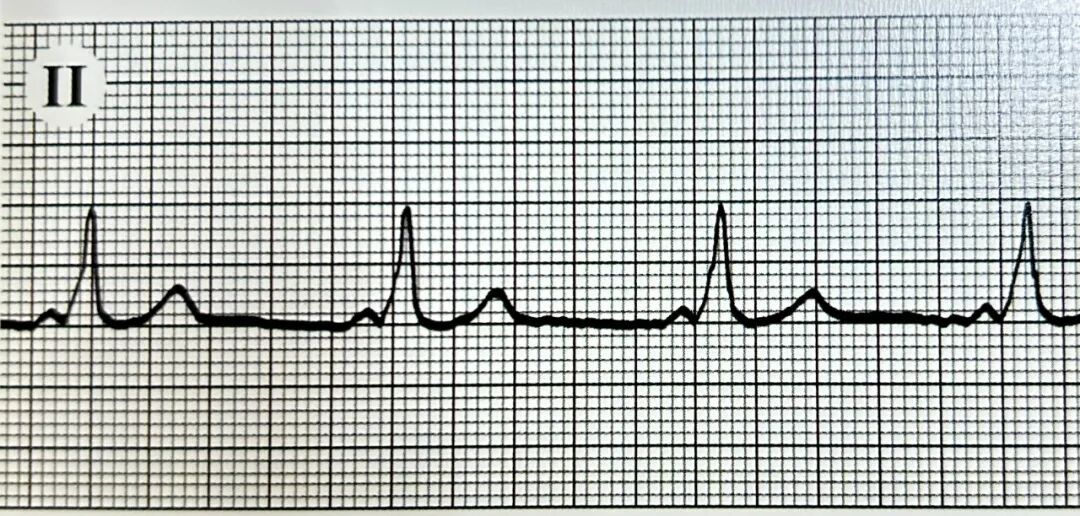

“心动”一

图中所示心电图最可能的诊断是()

“心动”密语:

1.每个QRS波前均可见相关的P波,P波在II导联直立,符合窦性心律。

2.具备心室预激的典型三联征:PR间期缩短<0.12秒(3小格)、QRS波增宽>0.11秒,起始部可见粗钝的Delta波。

临床意义:心室预激是房室旁路存在的一种电生理现象,其核心风险在于旁路可能构成折返环路,引发房室折返性心动过速(AVRT),或在合并房颤时将快速心房激动下传至心室,导致极快心室率,甚至进展为心室颤动。对于无症状者可临床观察,若频繁发作心动过速或属于高危旁路,则需评估导管射频消融术的必要性。